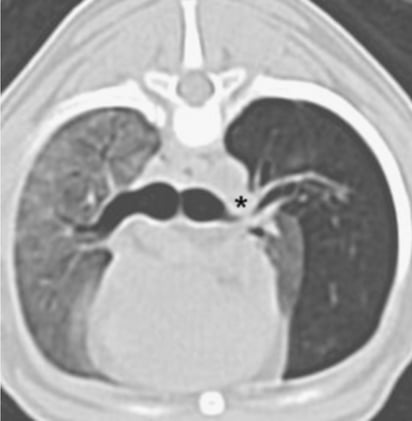

- CT

CT